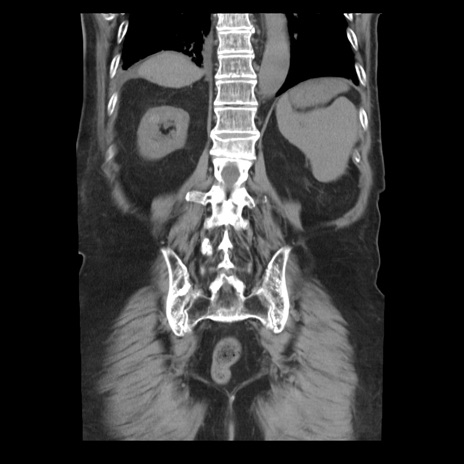

症例21(冠状断像)

【症例】70歳代男性

【主訴】腹痛

【現病歴】肝硬変・肝細胞癌にてかかりつけの方。約9時間前に食後より腹痛出現。症状が徐々に増悪し、嘔吐出現したため来院。

【既往歴】肝硬変、肝細胞癌(RFA、TACE後)

【身体所見】意識清明、表情苦悶様、BT 36℃、BP 129/78mmHg、P 88bpm、SpO2 97%(RA)、右上腹部から心窩部にかけて圧痛あり、反跳痛なし、筋性防御あり。

【データ】WBC 5800、CRP 0.16